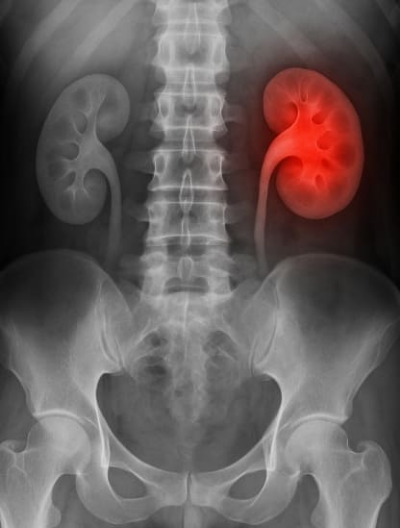

신우신염은 신장과 연결된 요관의 일부인 신우에 세균이 침입하면서 염증이 발생하는 질환입니다. 주로 요로감염에서 비롯되며, 방치할 경우 신장 기능 저하 또는 패혈증까지 진행될 수 있습니다. 신우신염 증상은 고열, 옆구리 통증, 빈뇨, 배뇨통, 탁한 소변 등으로 시작되며, 초기 진단과 치료가 매우 중요합니다. 오늘은 신우신염 증상과 신우신염 원인, 자가진단법, 치료 방법, 예방 생활수칙까지 통합적으로 정리해드리겠습니다.

신우신염은 신장의 일부인 신우(pelvis renalis)에 세균이 침투하여 염증이 발생하는 질환으로, 요로감염의 상행 감염 형태로 자주 나타납니다. 대부분의 신우신염은 대장균(E. coli)에 의해 발생하며, 방치 시 신장 기능 저하, 만성 신장염, 패혈증으로 이어질 수 있어 반드시 빠른 진단과 치료가 필요합니다.